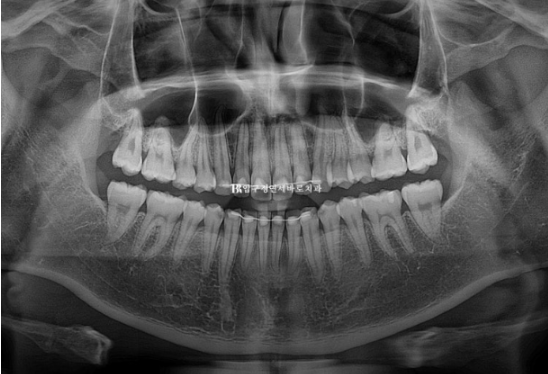

24.10

치근흡수는 없고 뿌리 평행도는 좋습니다.